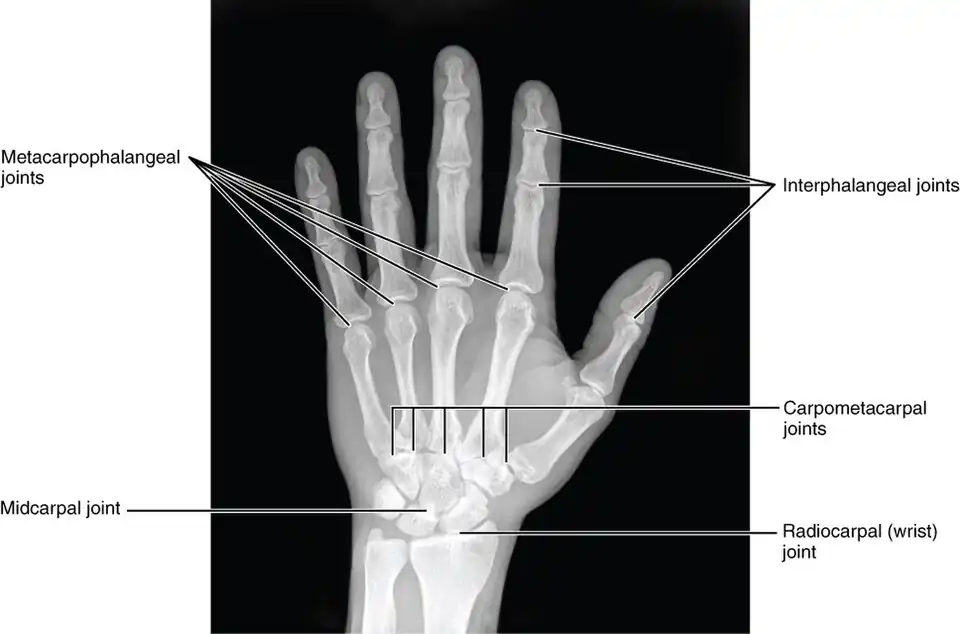

The interphalangeal joints of the hand are the hinge joints between the phalanges of the fingers that provide flexion towards the palm of the hand.

There are two sets in each finger (except in the thumb, which has only one joint):

- "proximal interphalangeal joints" (PIJ or PIP), those between the first (also called proximal) and second (intermediate) phalanges

- "distal interphalangeal joints" (DIJ or DIP), those between the second (intermediate) and third (distal) phalanges